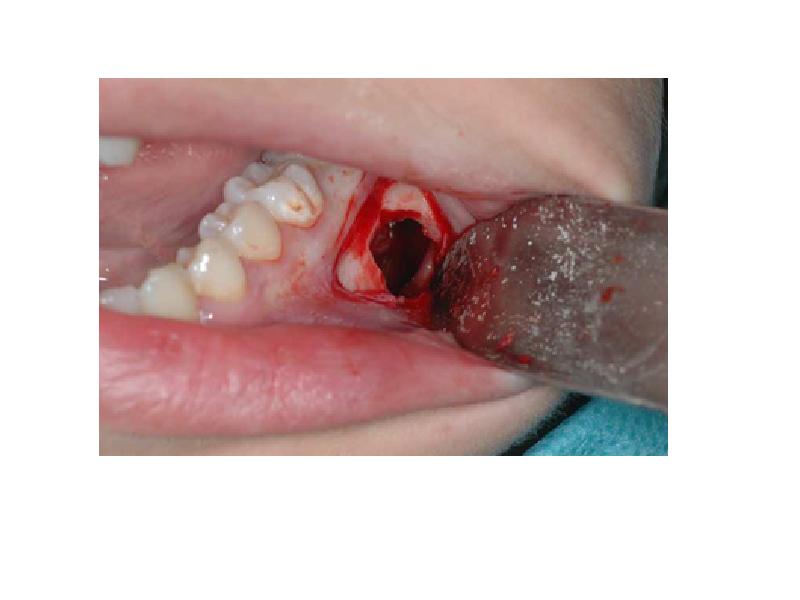

- 86. Аневризмальная костная киста Расширенное остеолитическое поражение Возраст пациентов обычно до

- 88. Исходы Вероятно эта киста в дальнейшем будет отнесена к опухолям (стабильная

- 89. Посттравматическая костная киста Несмотря на название связи с травмой при образовании